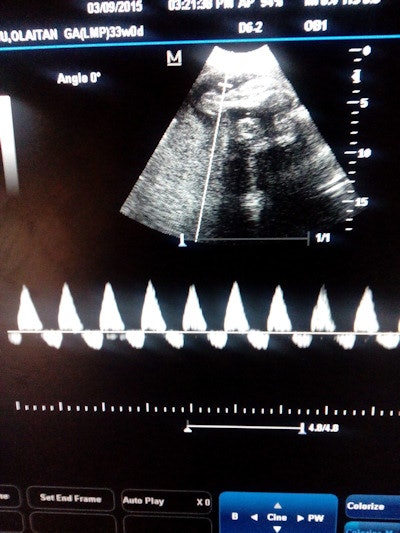

Ultrasound case sent via WhatsApp for remote expert consultation. All images courtesy of Dr. Victor Oboro from Ladoke Akintola University of Technology and Omvial 4D Ultrasound.

Ultrasound case sent via WhatsApp for remote expert consultation. All images courtesy of Dr. Victor Oboro from Ladoke Akintola University of Technology and Omvial 4D Ultrasound.What's more, patients appreciated the opportunity to have such easy access to remote expert consultations, according to lead investigator Dr. Victor Oboro of Ladoke Akintola University of Technology in Ogbomoso, Nigeria.

In another case that sadly ended in tragedy, a sonographer performing a fetal heart assessment believed there was something unusual about the heart and sent the image as a video clip (see below) via WhatsApp for remote analysis.

|

Click image to view video. |

In the meantime, however, the referring physician had sent the patient to another sonographer for a second opinion. Although the second sonographer indicated that the heart was "normal," the remote fetal medicine ultrasound experts reported that the fetus was having heart failure, Akinmoladun said.

The baby appeared clinically normal at delivery and no further action was taken by the referring physician. After reviewing the case again, the experts were sure that the heart was failing and tracked down the mother to advise her to take the baby for pediatric echocardiography. Unfortunately, the mother informed them that the baby had died three days after birth.